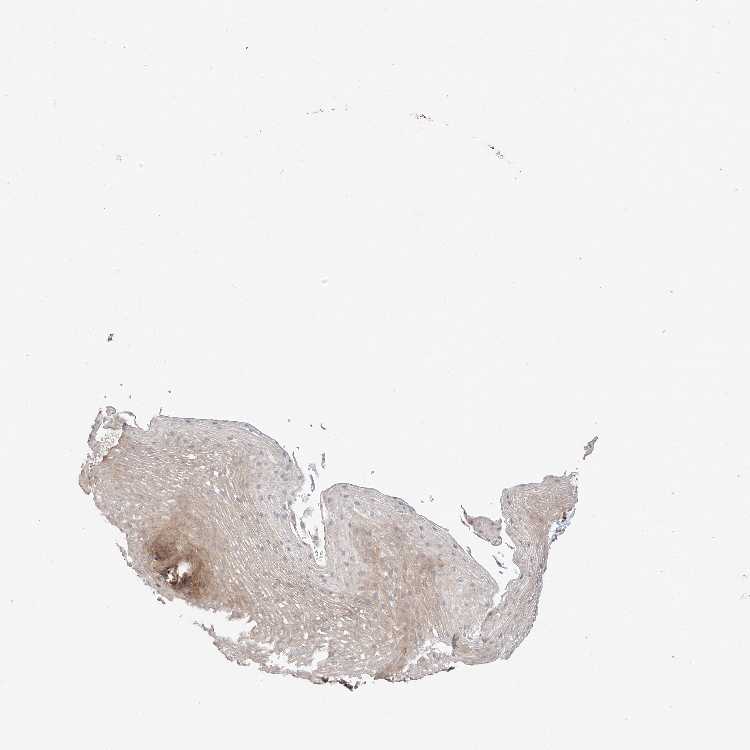

ESOPHAGUS - Antibody stainingi

Antibody staining in the annotated cell types in the current human tissue is reported as not detected, low, medium, or high, based on conventional immunohistochemistry profiling in selected tissues. This score is based on the combination of the staining intensity and fraction of stained cells.

Each image is clickable and will lead to virtual microscopy that enables deeper exploration of all samples and also displays staining intensity scores, fraction scores and subcellular localization as well as patient and tissue information for each sample.

Antibody HPA030419Antibody HPA030420Antibody HPA030422Antibody CAB025196Antibody CAB080286Antibody CAB080287

Squamous epithelial cells Not detectedNot detectedHighMediumMediumLow